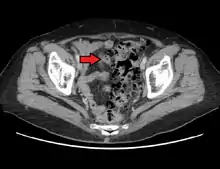

Imaging

- Contrast CT is the investigation of choice in acute episodes of diverticulitis and where complications exist.

- Colonoscopy will show the diverticulum and rule out malignancy. A colonoscopy should be performed 4–6 weeks after an acute episode.